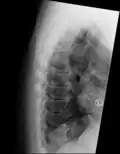

DISH in an 80 year old female, also with T11 fracture.

DISH is diagnosed by findings on x-ray studies. Radiographs of the spine will show abnormal bone formation (ossification) along the anterior spinal ligament. The disc spaces, facet and sacroiliac joints remain unaffected. Diagnosis requires confluent ossification of at least four contiguous vertebral bodies.[2] Classically, advanced disease may have "melted candle wax" appearance along the spine on radiographic studies.[13] In some cases, DISH may be manifested as ossification, or enthesis, in other parts of the skeleton.